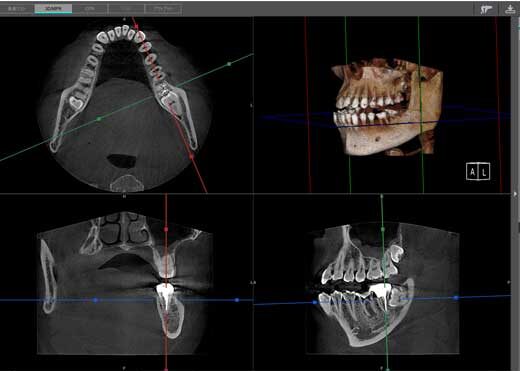

根管の形状は非常に複雑で、通常のレントゲン写真では完全に把握することができません。従来のレントゲンは二次元の画像であるため、根管の立体的な構造や分岐を正確に捉えることができないのです。

歯科用CT(コーンビームCT)は、歯の三次元的な構造を詳細に撮影できる装置です。これにより、複雑な根管形態や通常のレントゲンでは発見できない病変を事前に把握することができます。

私が日々の診療で実感するのは、CTを使用することで治療前の診断精度が格段に向上するということです。例えば、レントゲンでは見えなかった副根管や複雑な湾曲が明確に確認でき、それに応じた治療計画を立てることができます。

CTを導入している歯科医院は、精密な診断と治療にこだわりを持っている証拠です。根管治療を受ける際は、歯科用CTを活用しているかどうかも重要なチェックポイントとなります。